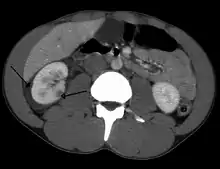

Abdominal trauma resulting in a right kidney contusion (open arrow) and blood surrounding the kidney (closed arrow) as seen on CT | |